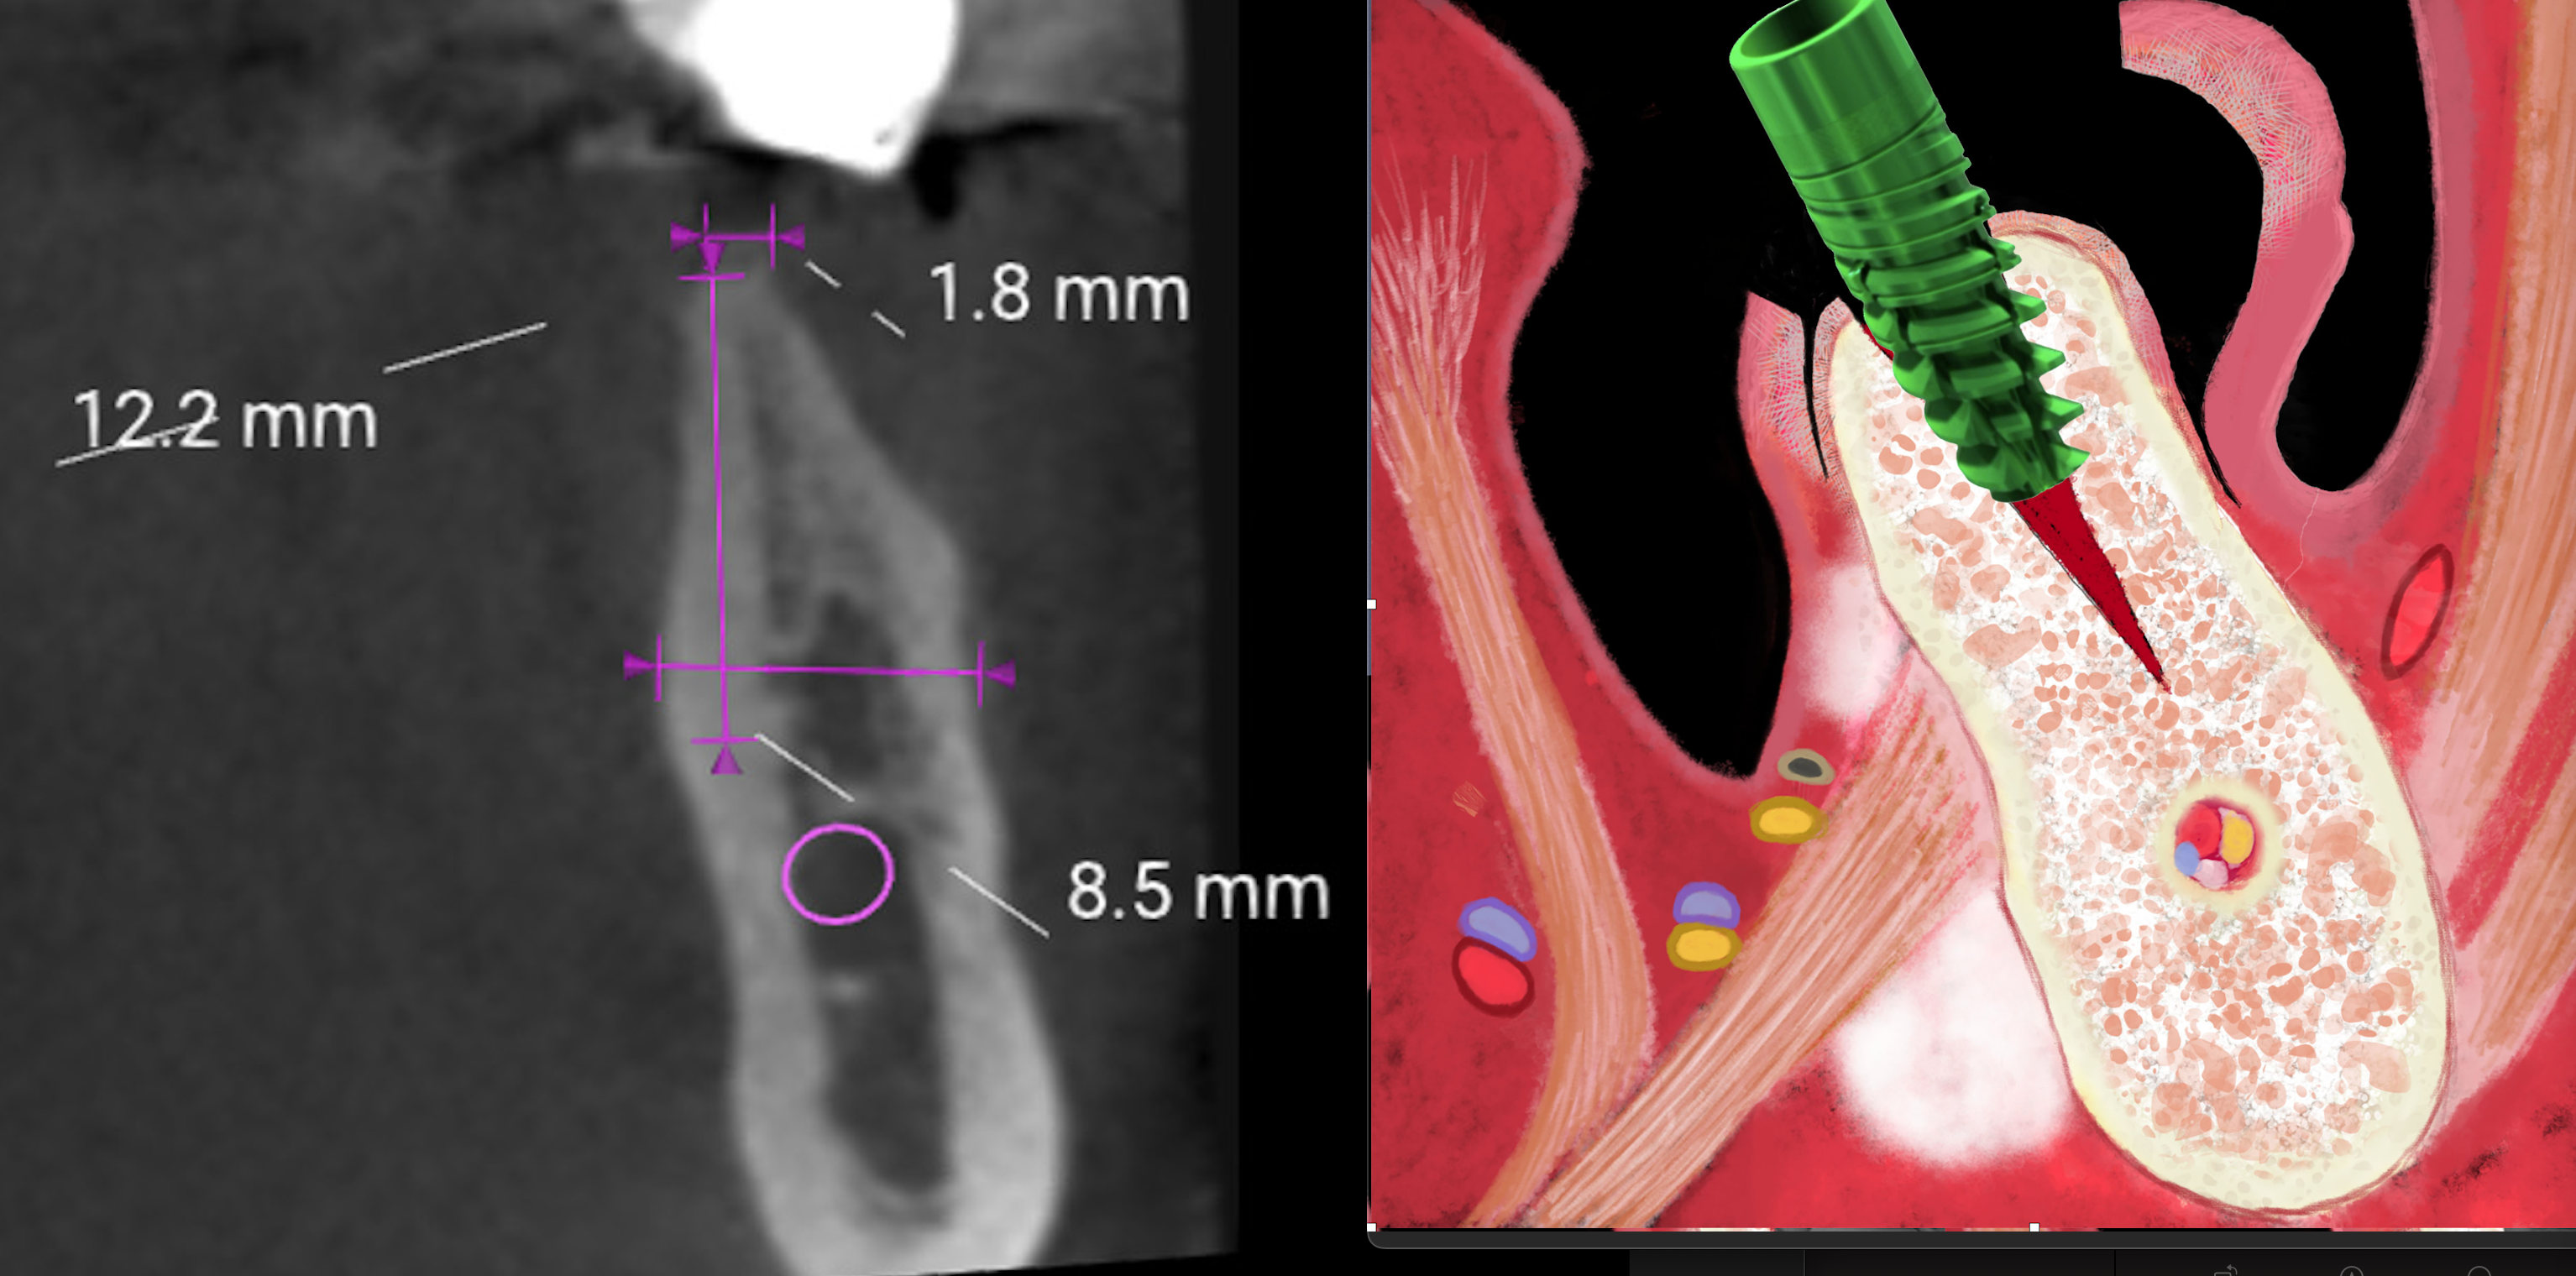

Split Crest ERE: 98.1% Successo ma “non funziona”

Meta-analisi 2023 su 1.400 impianti dimostra 98.1% di sopravvivenza con split crest (ERE). Scopri perché le critiche all’espansione crestale nascondono interessi economici e conflitti d’interesse. Dati scientifici vs opinioni non supportate.